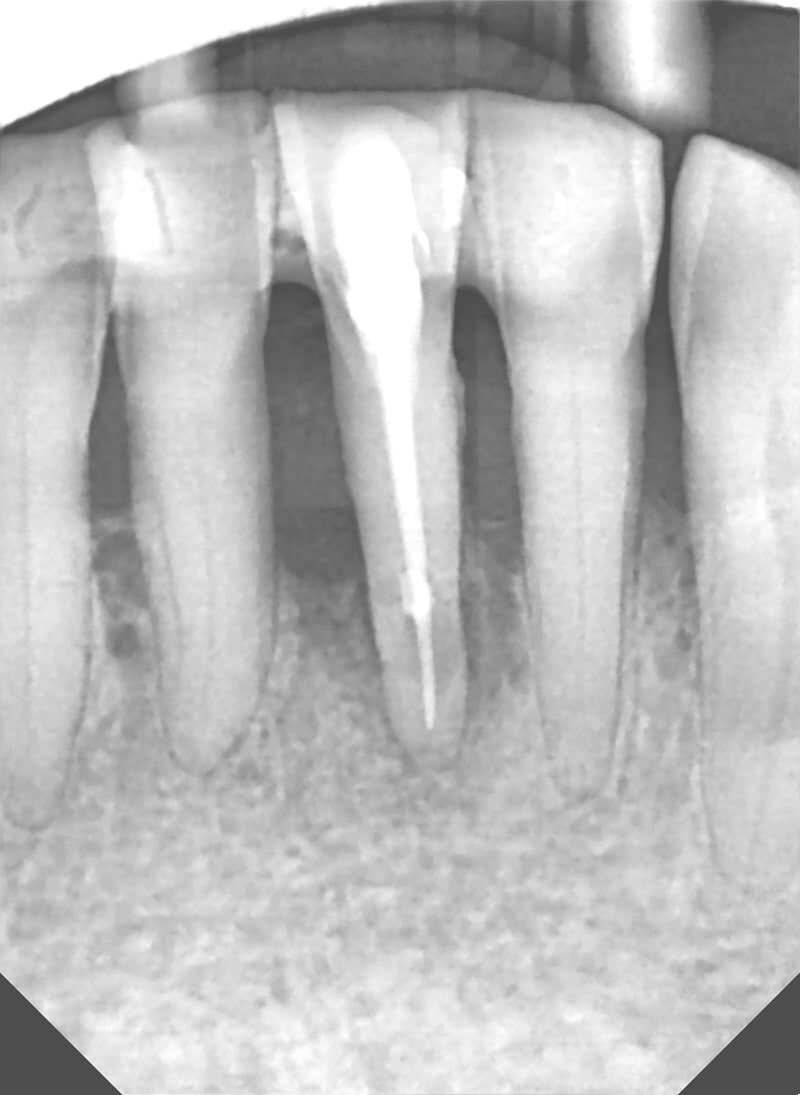

tu aurais une radio des dents restantes ?

voici le cliché

Ok, on a encore un rapport couronne/racine de 1/1 environ. Même si la 42...